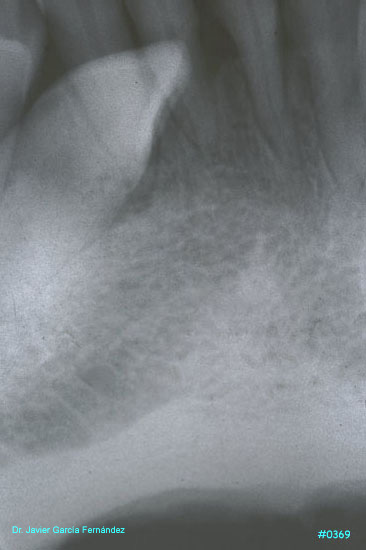

ATLAS DE CIRUGIA PERIODONTAL

image419